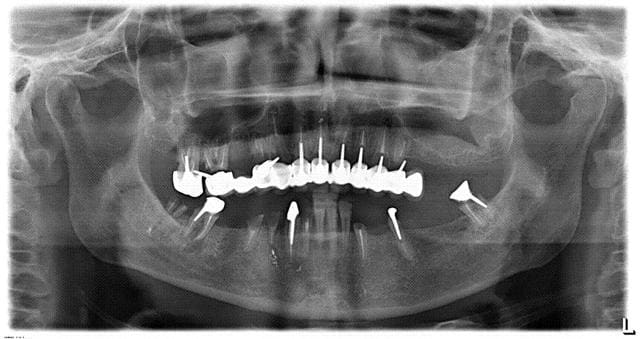

bridges max et mand faits il y a deux ans de ça au pays basque

là je crois qu'on bat tout le monde